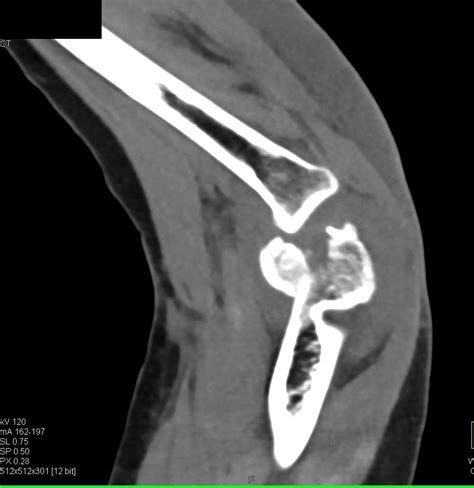

Comminuted Fracture: Symptoms, Causes & Treatment

Source: www.painmedicinesnews.com